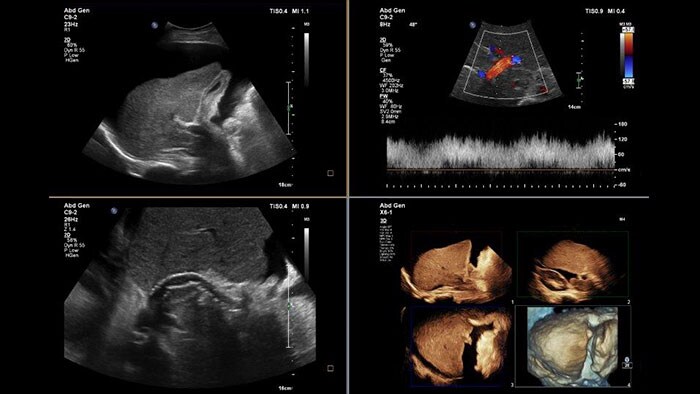

US Q-App General Imaging 3D Quantification (GI3DQ)

Perform advanced visualization and quantification of ultrasound volume

US Q-App General Imaging 3D Quantification (GI3DQ) provides advanced viewing, manipulation, and quantification of 3D data sets. Perform advanced functions such as MPR interrogation, iSlice tomographic imaging, and volume rendering as well as volumetric measurements using multiple methods including semi-automated tools. Results generated from this tool can be appended to the patient’s exam for complete documentation.

Benefits

- Advanced viewing, manipulation, and analysis of 3D ultrasound data.

- Perform multi-planar reconstruction, iSlice tomographic imaging, and advanced rendering functions.

- Easily generate 2D and volume measurements using semi- automated analysis tools.

- Compatible with 3D datasets from Philips EPIQ, Affiniti, iU22, HD15, HD11 and HD9 systems.